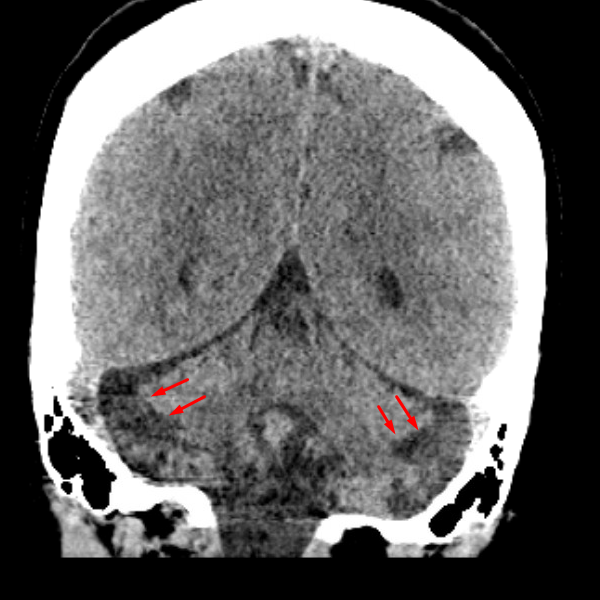

Age: 37

Sex: Female

Indication: Headache